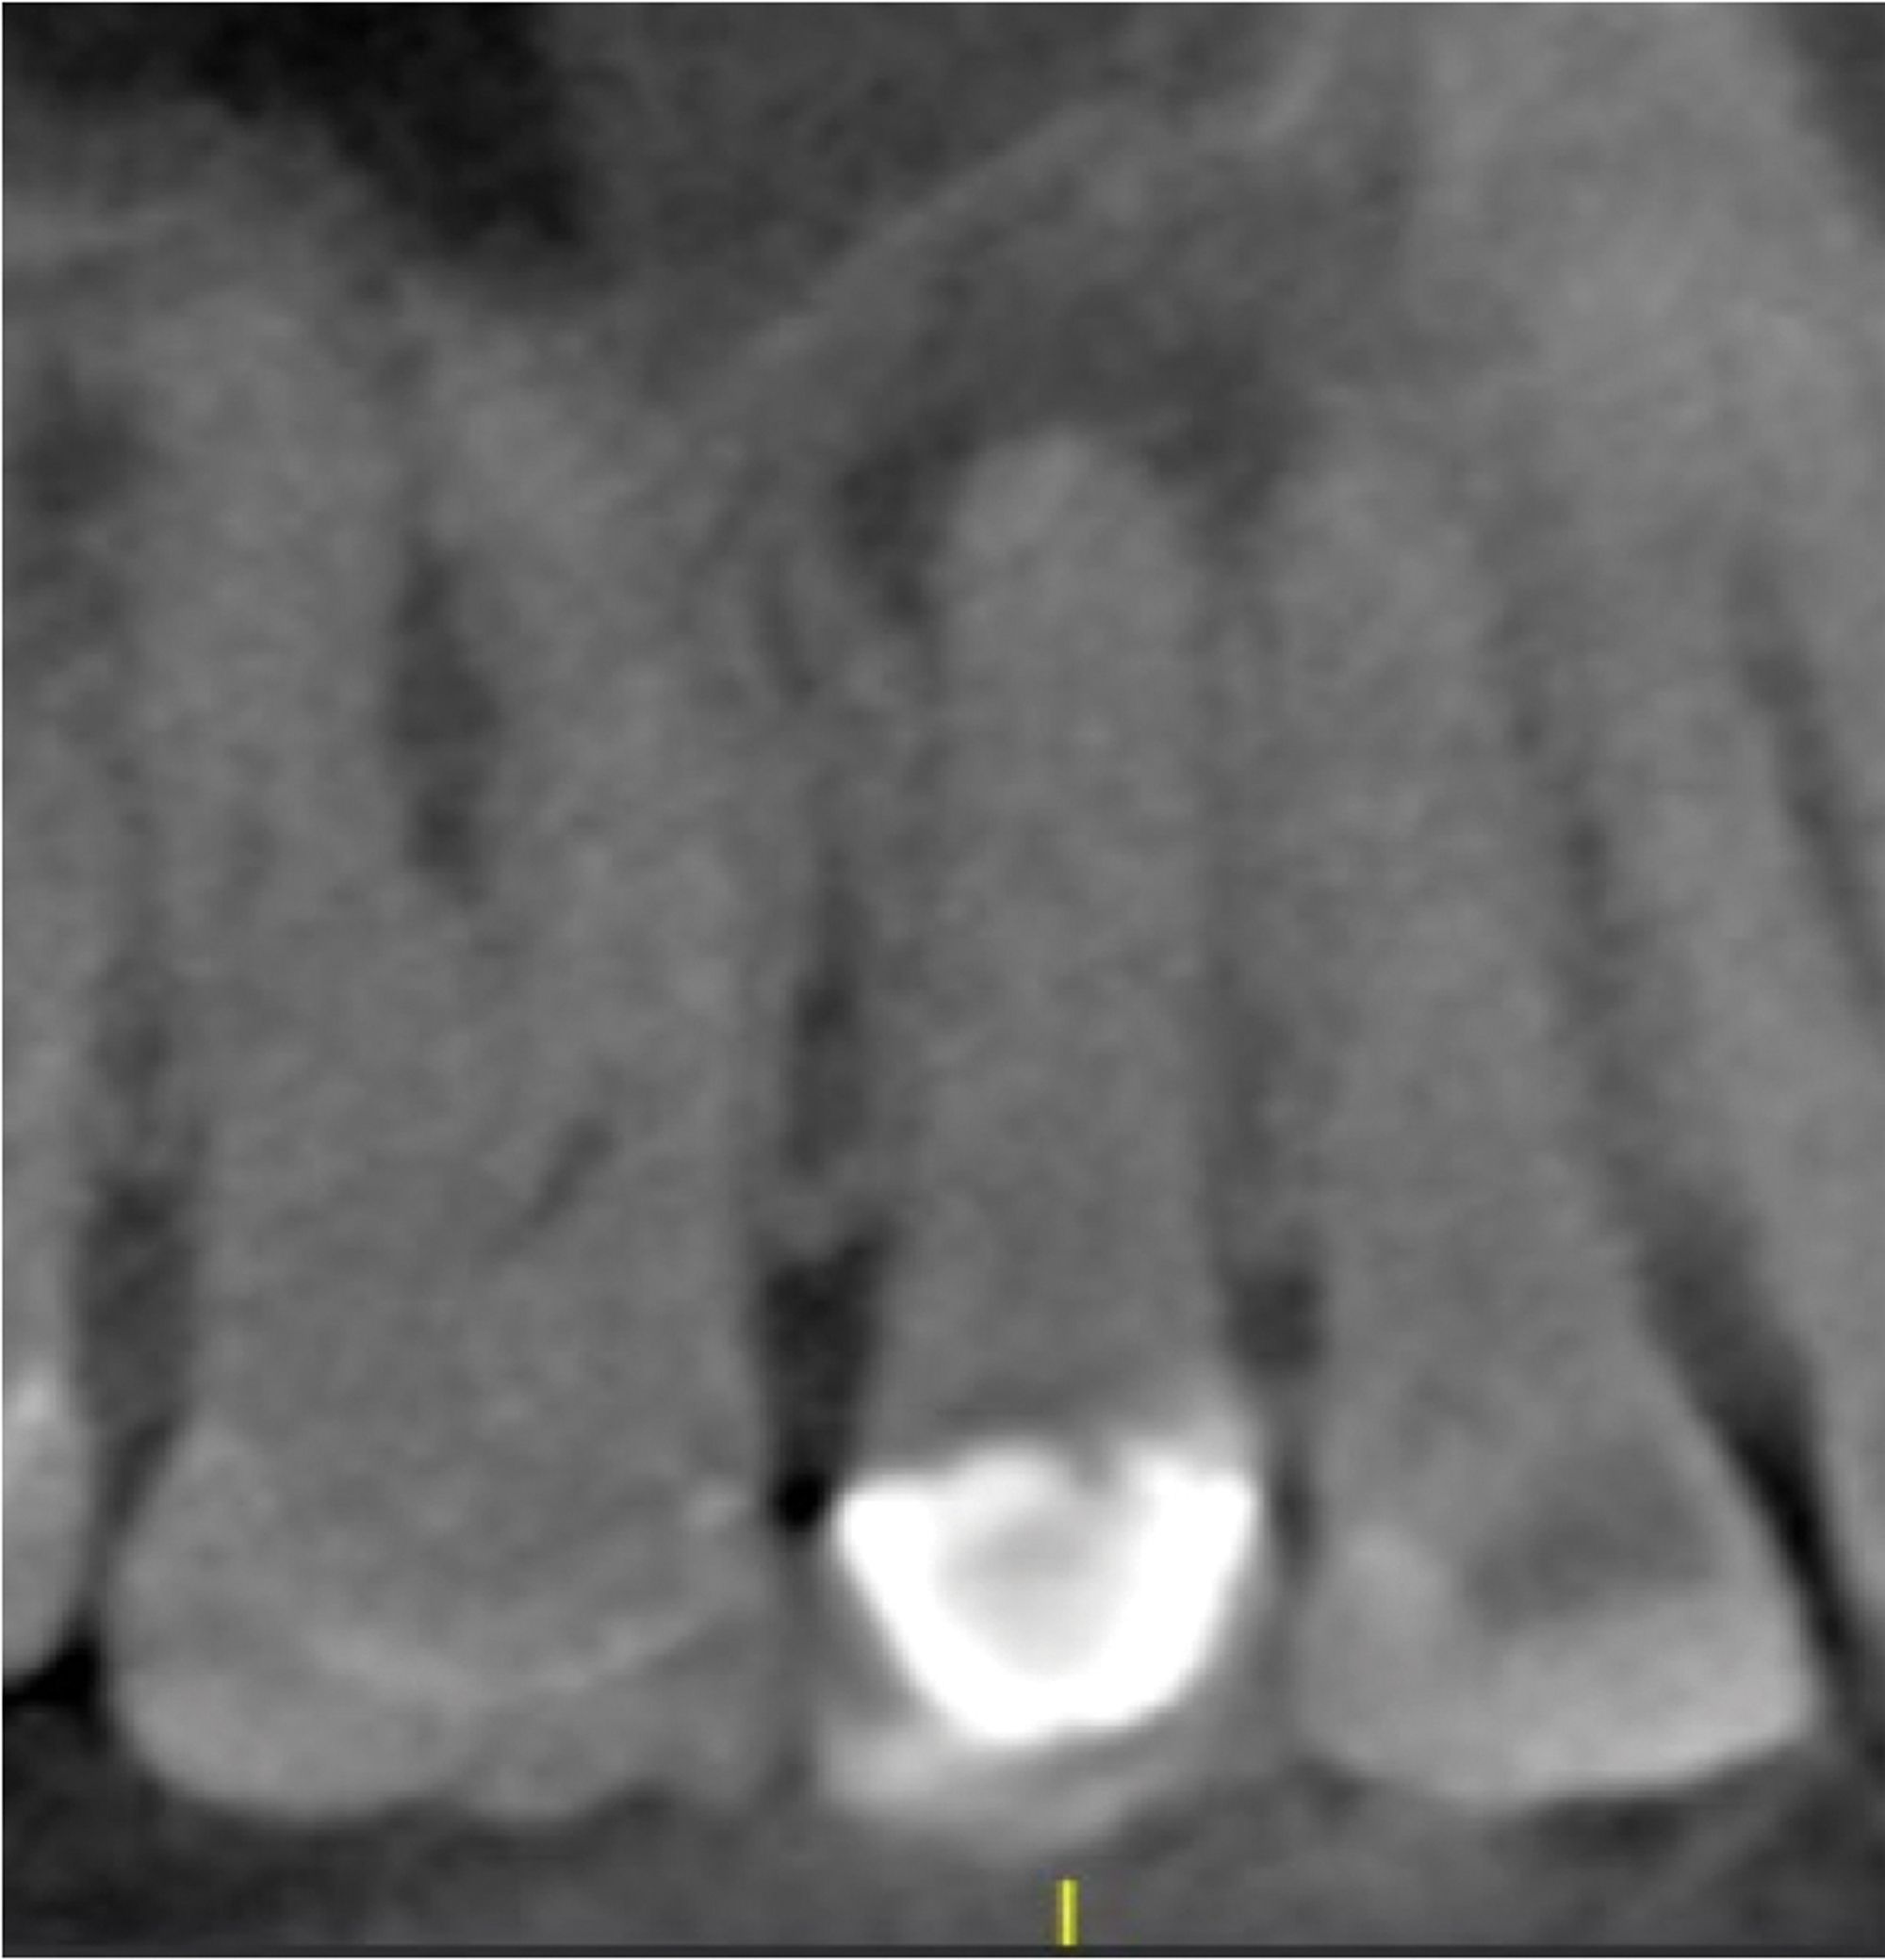

Endodontic Healing Potential 8Month Progress Renovo Endodontic Studio

Endodontic Healing Potential 8Month Progress Renovo Endodontic Studio Endodontic Treatment Hypertension the aim of this article is to review the newest recommendations for patients with these disorders who require. the results of the present study conclude that prevalence of apical periodontitis and endodontic treatment is not significantly. this study aimed to assess the mean percentages of systolic, diastolic, and arterial blood pressure (msbp, mdap,. and practice standards. Endodontic Treatment Hypertension.